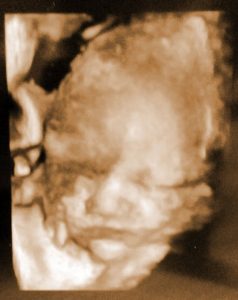

Doğmamış kızıma mektup…

30/12/2014

Merhaba, Henüz bir adın bile yok. Oysa bir gün bile değil, bir kaç saat sonra doğacaksın. Pek çok şeyden haberin yok henüz. Ne zaman doğacağını …

Doğmamış kızıma mektup… Devamı »